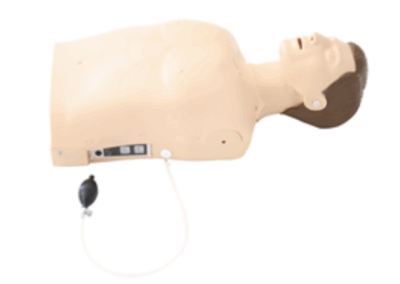

Simuladores de Habilidades Clínicas

Treinamento prático em procedimentos médicos essenciais.